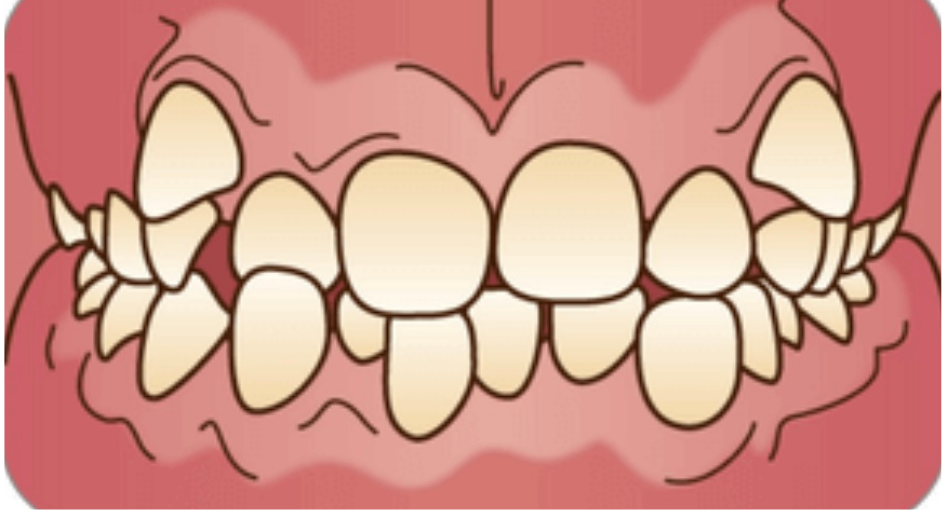

歯列不正のよくある例Examples of malaligned teeth

叢生(そうせい)

歯と歯が重なっている、カタカタしている